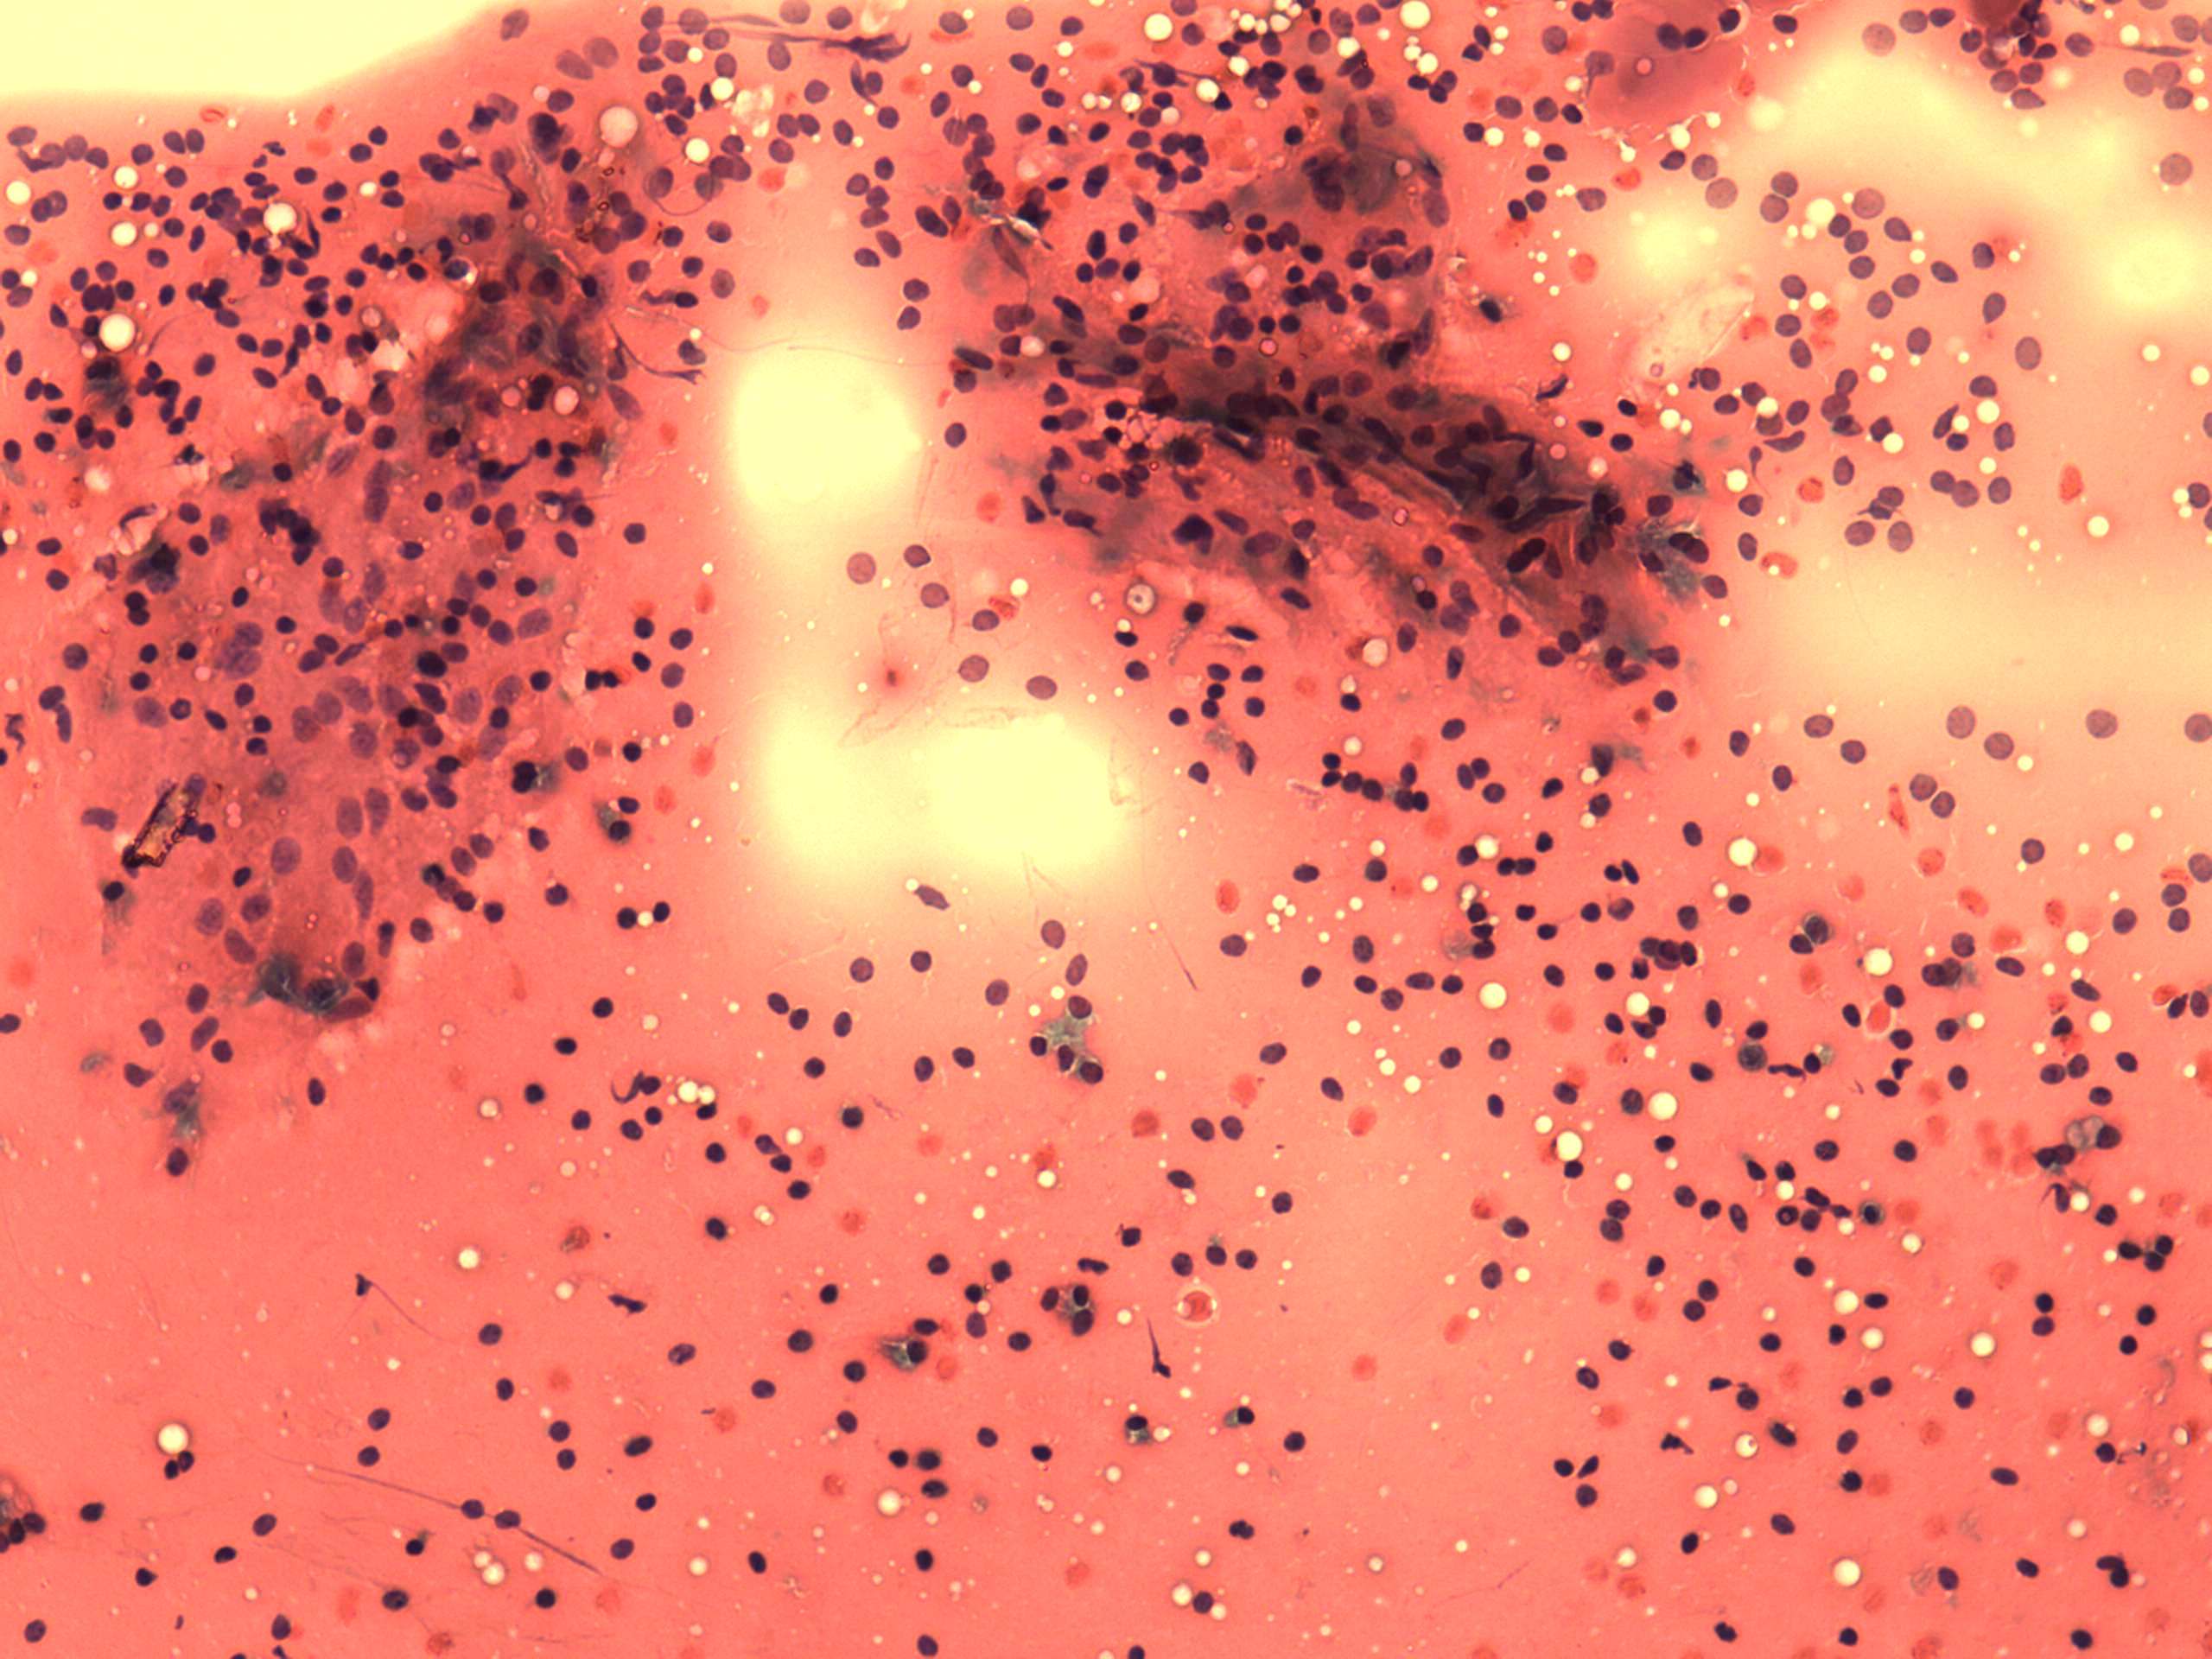

Benign nodular hyperplasia - Case 38. (cytologic picture 4)

Pap-smear, 400x. Pycnotic nuclei in colloidal background.